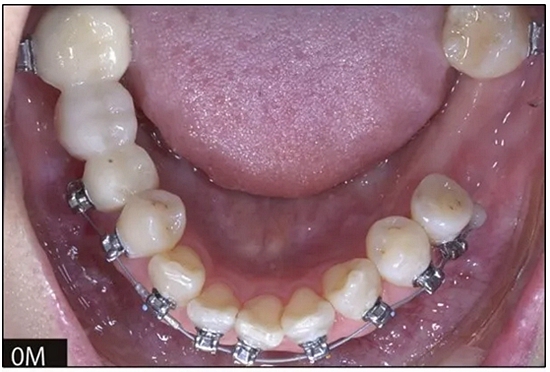

完全固定的Damon Q設(shè)備(加利福尼亞州Glendora的Ormco)與制造商指定的弓絲和附件一起使用。下頜弓,一開始放入0.014英寸的鎳鈦弓絲,5個月后放入0.014×0.025英寸的鎳鈦弓絲。舌側(cè)扣和鏈圈放置在下頜尖牙和第二前磨牙上以控制扭轉(zhuǎn)。在治療的第7個月,將下頜弓絲換成0.017× 0.025英寸的β鈦絲。另一個舌側(cè)扣和鏈圈放置在下頜左側(cè)第三磨牙上以提供近中牽引力(圖9)。在16個月的治療結(jié)束時,所有的扭轉(zhuǎn)都得到了矯正,缺牙間隙縮小到8 mm(圖8),但由于頰側(cè)骨板的嚴重吸收,牙槽嵴的寬度仍然很窄(約3 mm)(圖9)。通過正畸移動下頜左側(cè)第二前磨牙,在前磨牙之間產(chǎn)生一個種植部位。在第一和第二前磨牙之間的弓絲上放置一個推簧,并將舌側(cè)扣和鏈圈放置在第一前磨牙和第三磨牙之間(圖9),在頰側(cè)和舌側(cè)施加力。施力均為輕力,每個表面上約2盎司(28.3 cN)以控制牙根側(cè)面的吸收。

圖8